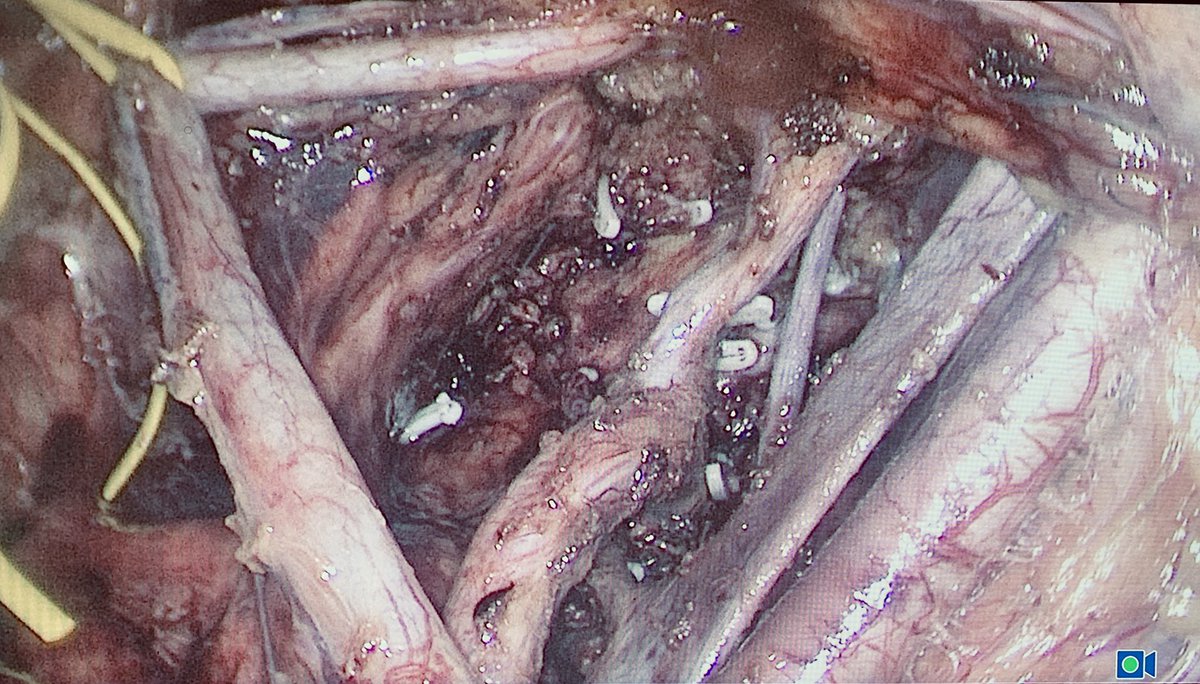

Technical #challenge case in #colorectal surgery at Cirugía General Hospital Italiano de Buenos Aires. Laparoscopic #TME and Lateral node dissection for distal #rectalcancer after neoadjuvant chemoradiation, performed with Juan Pablo Campana and Ricardo Mentz. Example of #teamwork and multidisciplinary management!